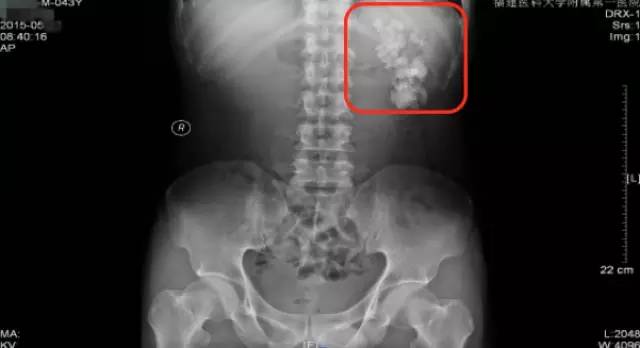

柯先生慕名来到我的门诊就诊。简单询问病情后,我给他开了KUB的检查单,KUB结果如下:

可见相当于左肾区(红框内)多发结节状密度增高影聚集,部分呈鹿角型。这是一个非常复杂的肾结石,虽然还没有做CT检查,但已可以判断这个肾脏功能一定受损严重,当时就建议柯先生住院微创手术治疗。

第一次来福建医科大学附属第一医院KUB检查结果

可见相当于左肾区(红框内)多发结节状密度增高影聚集,部分呈鹿角型